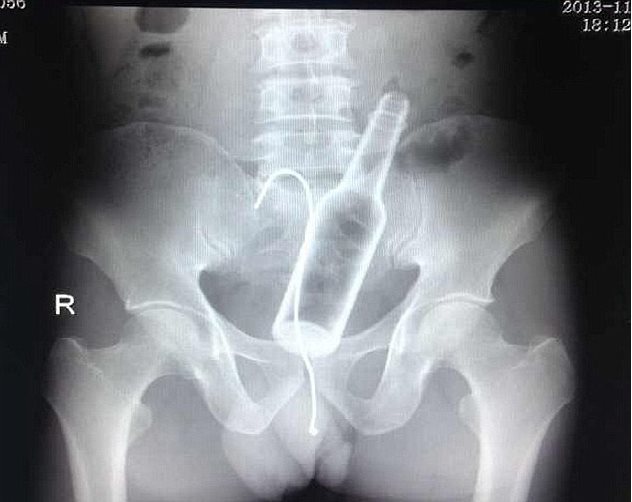

Σφήνωσε μπουκάλι στα οπίσθια του και προσπάθησε να το τραβήξει με… αγκίστρι!

Ρεζίλι των σκυλιών έγινε ένας άντρας στο νοσοκομείο Φουτζού της επαρχίας Φουτζιάν στην Κίνα, όταν πήγε για να κάνει ακτινογραφίες και ανακάλυψαν οι γιατροί ότι είχε μπει στον πρωκτό του ένα μπουκάλι και μαζί το αγκίστρι του ψαρέματος! Ο Κινέζος βρισκόταν στο σπίτι του και για κάποιο λόγο θέλησε να δει αν χωράει ένα μπουκάλι στον πρωκτό του και το έχωσε τόσο βαθιά που του ήταν αδύνατο να το βγάλει με το χέρι. Έτσι, για να το τραβήξει πήρε καλάμι ψαρέματος, έβαλε το αγκίστρι του στο μπουκάλι που ήταν μέσα του και άρχισε να τραβάει.

Όμως, δεν τα κατάφερε και αναγκάστηκε να ζητήσει βοήθεια από γιατρούς, οι οποίοι έμειναν άναυδοι όταν αντίκρυσαν τις ακτινογραφίες. Τελικά, μετά από εγχείρηση κατάφεραν να εξάγουν όλα τα αντικείμενα που είχαν χωθεί εκεί μέσα!